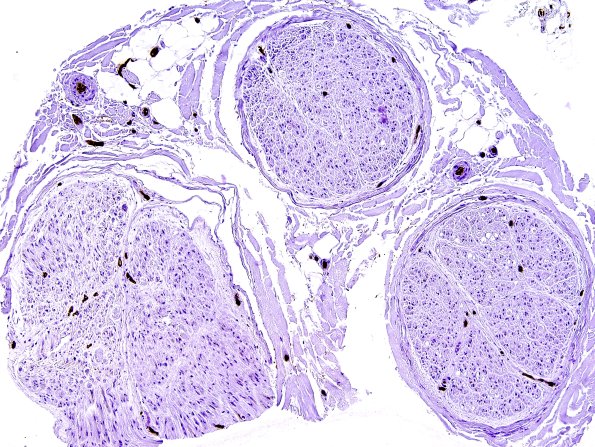

10A Normal Nerve (Case 9) Ulex 1

Ulex staining of an additional sural nerve. (Ulex lectin)